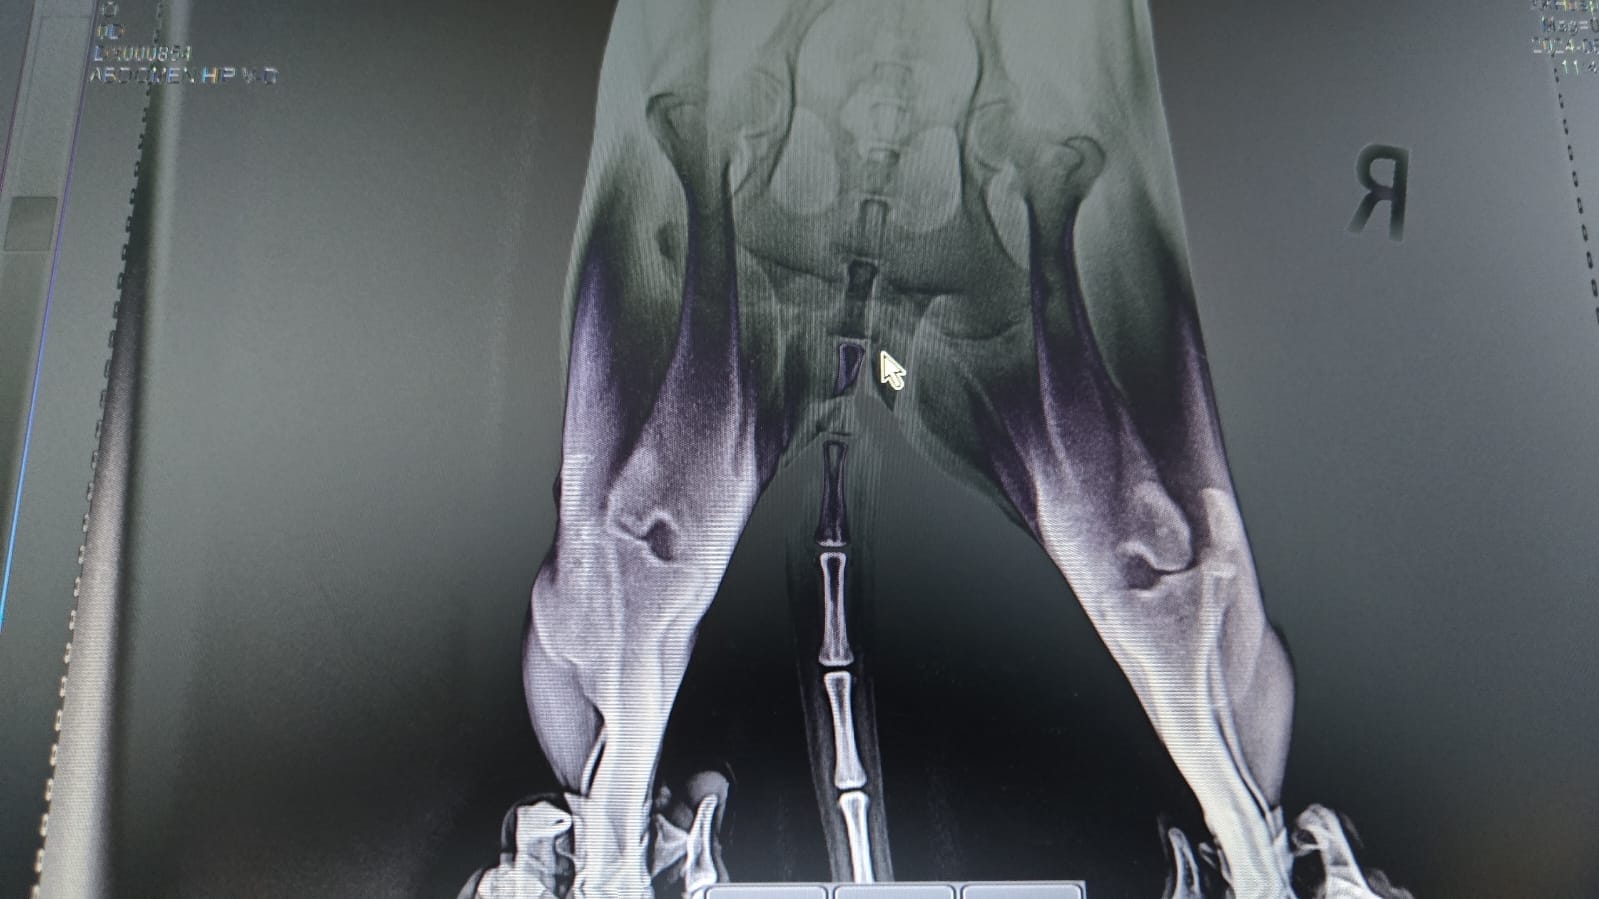

Someone had slammed her back end into the ground with the force of a boot. The trauma forced both her knees sideways.

Under the guidance of a university professor of veterinary medicine, our orthopedic surgeon performed a complex and delicate operation to repair the damage. The surgery itself was a success, and for a brief time, there was hope that she might reclaim some of the life stolen from her.